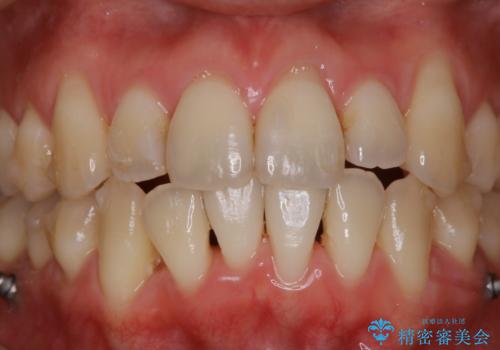

インビザライン中の方 結婚式前にPMTCでステインの除去

- インビザラインでの矯正治療中ですが、結婚式があるため全体の着色・ステインを綺麗にしたいとのことでした。PMTC60分コースを行いました。

またPMTCを行うことで、ご自身本来の歯の色になり自然な明るさになります。

口元が自然な明るさになることで、より清潔感のある印象になるため結婚式・行事やイベント前などにもPMTCを行うはおすすめです。